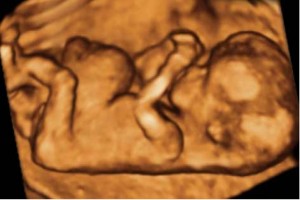

Diplomados en Ultrasonografía